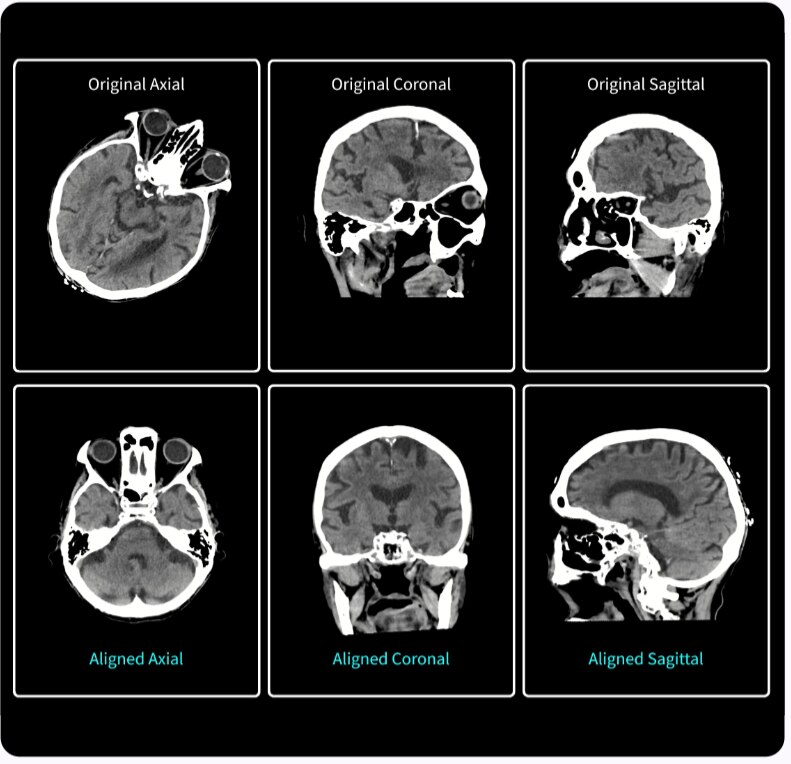

KULLANICI ARAYÜZÜ

Otomatik olarak sezgisel

Revolution Ascend'i kullanıma sunarak, birinci sınıf BT sistemimizle aynı kullanıcı arayüzünü (UI) dahil ediyor ve işlevleri standartlaştırmaya başlıyoruz. Kullanıcı Arayüzü, akıllı anatomi tanıma ve lokalizör ayarları için Smart Plan gibi özelliklerle günlük ihtiyaçlarınız düşünülerek tasarlanmış yeni Clarity Operatör Ortamına sahiptir. Ek olarak Auto Prescription, uzmanlık düzeyinizden bağımsız şekilde hastaya özel tarama parametreleri önererek tarama kurulumunu ayarlar ve tüm taramalarda istenen görüntü kalitesi ve doz performansını sağlar.

Kaliteden ödün vermeden kapsamlı ayrıntı, üstün kontrast, doku ve görüntü netliği sağlar.